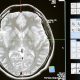

El lóbulo parietal, un potencial aliado en la lucha contra el alzhéimer